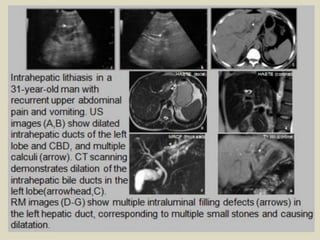

Stones in the ducts Probably the most common biliary

tract disease is duct stones, which occur in 8% to 20%

of patients undergoing cholecystectomy and 2% to 4%

of patients after cholecystectomy. Small calculi may

intermittently cause colicky pain as they obstruct at

the ampulla of Vater, but generally pass into the

duodenum. Larger stones 5 to 10mm are difficult to

pass and can result in intermittent long-term

obstructive symptoms and sequelae, such as

cholangitis and sepsis. Detecting stones in the ducts is

easiest when biliary dilatation is also present.

Unfortunately, because biliary dilatation is present in

only about two-thirds to three-fourths of patients, it

can be difficult to image stones in many patients.